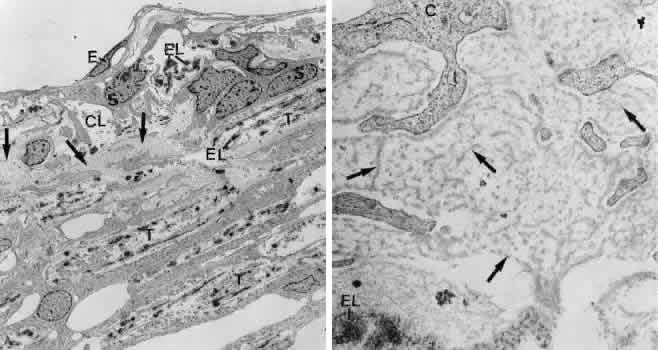

There are three different types of tendons by which the anterior ciliary muscle tips are connected with the TM or the corneosclera. Type I tendons derive from the outermost longitudinal muscle bundles and enter the sclera or the scleral spur to fix the muscle to the external tunica of the eyeball (Fig. 18). Type II tendons pass the scleral spur to anchor within the TM. They consist of elastic-like fibers that bend into the outer part of the TM and finally join the subendothelial network of elastic-like fibers described earlier. Type III tendons are of collagenous nature. They represent broad, elongated bands that penetrate the TM and insert within the corneal stroma.21,42 The tendons represent the main fixation of the entire ciliary muscle system to the external tunica of the eyeball and therefore seem to be important in the accommodation mechanism. The tendons may also help to expand the system of trabecular lamellae, so that the intertrabecular spaces remain open or enlarge if the ciliary muscle moves forward and inward. Regarding the outflow resistance, this would have little effect in normal eyes.

Fig. 18. Connections of the ciliary muscle (CM) with the trabecular meshwork (TR). Note the different types of muscle tendons (T) connected with the cornea or the elastic-like fiber network of the cribriform layer (EL), which on the other hand is connected with the inner wall endothelium (E) of Schlemm's canal (Sc) by connecting fibrils (CF). SP, scleral spur.

The main effect on aqueous outflow resistance seems to result from actions of the elastic-like type I and II tendons. Because the type I tendons connect the outermost ciliary muscle fiber bundles to the scleral spur, muscle contraction leads to a backward movement of the scleral spur followed by a change in the form of the outflow pathways (Fig. 19).21,42 Inward movements of the type II tendons during muscle contraction have a similar effect. It seems that normally parts of the cribriform layer (including their preferential aqueous pathways) are collapsed so that only a portion of the filtration area is functional. After ciliary muscle contraction the cribriform elastic-like fiber network is pulled inwardly and the connecting fibrils are straightened so that the entire cribriform layer expands. In addition, the lumen of Schlemm's canal is enlarged so that finally the filtering area increases and outflow resistance decreases (Fig. 20).